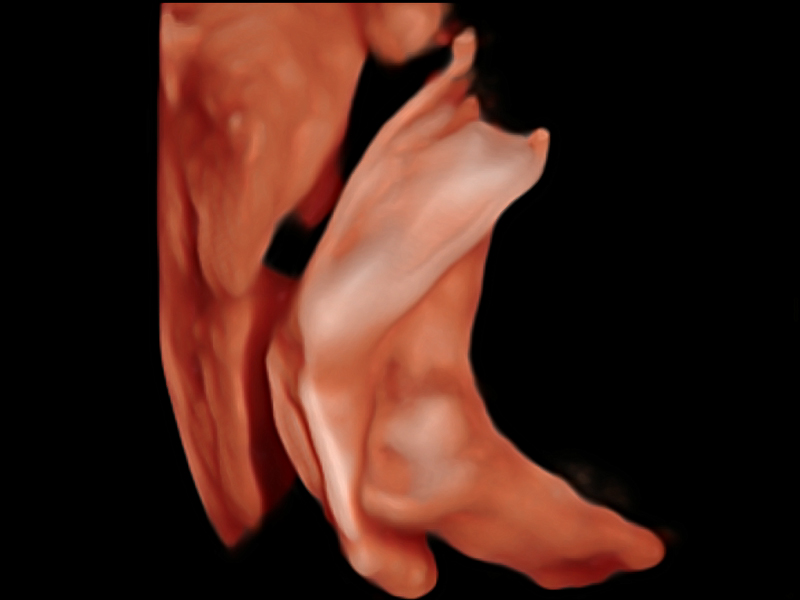

临床图像

• 产科扫查助手S-Fetus

S-Fetus基于大数据深度学习算法,能够帮助您在产前筛查过程中智能识别胎儿标准切面、自动测量并录入报告。一个按键,即可智能、精准、高效地获取胎儿生理指标,极大简化您的产科检查操作。